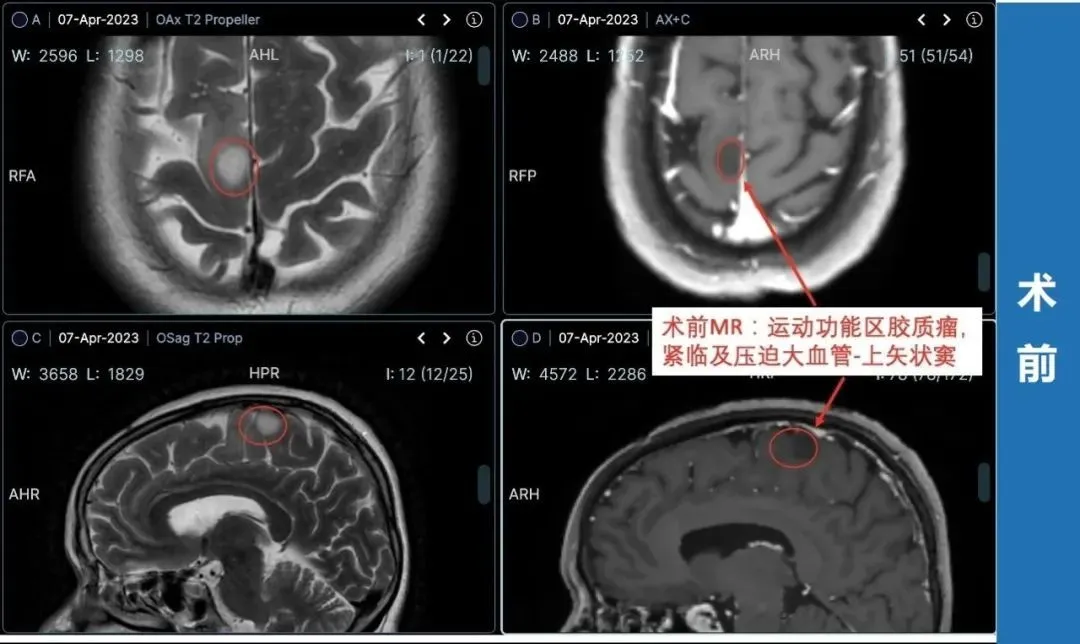

▼患者术前情况:2023年1月底罗女士突然左腿失去知觉摔倒,后面又类似情况发生几次。3月份,他们来到当地医院进行检查,颅脑MR+增强显示:右侧额叶异常信号灶,考虑低级别胶质瘤。当地医生建议:目前肿瘤比较小,手术怕伤到运动神经,也怕切不干净,先保守治疗,等腿和手的功能都出现障碍了,为了保命延长生存期不得已时再做手术。此时正恰逢巴教授中国行期间,他们便立马通过INC紧急整理资料咨询巴教授。

▼治疗过程:4月2日,罗女士和家人一致决定找巴教授手术,这时距离罗女士咨询巴教授仅过去了2天。

最终,INC德国巴特朗菲教授为额叶胶质瘤合并癫痫发作患者——66岁的罗女士顺利行肿瘤切除,在术中导航、术中核磁、术中神经电生理监测下,肿瘤取出的同时也保护了大脑正常功能。